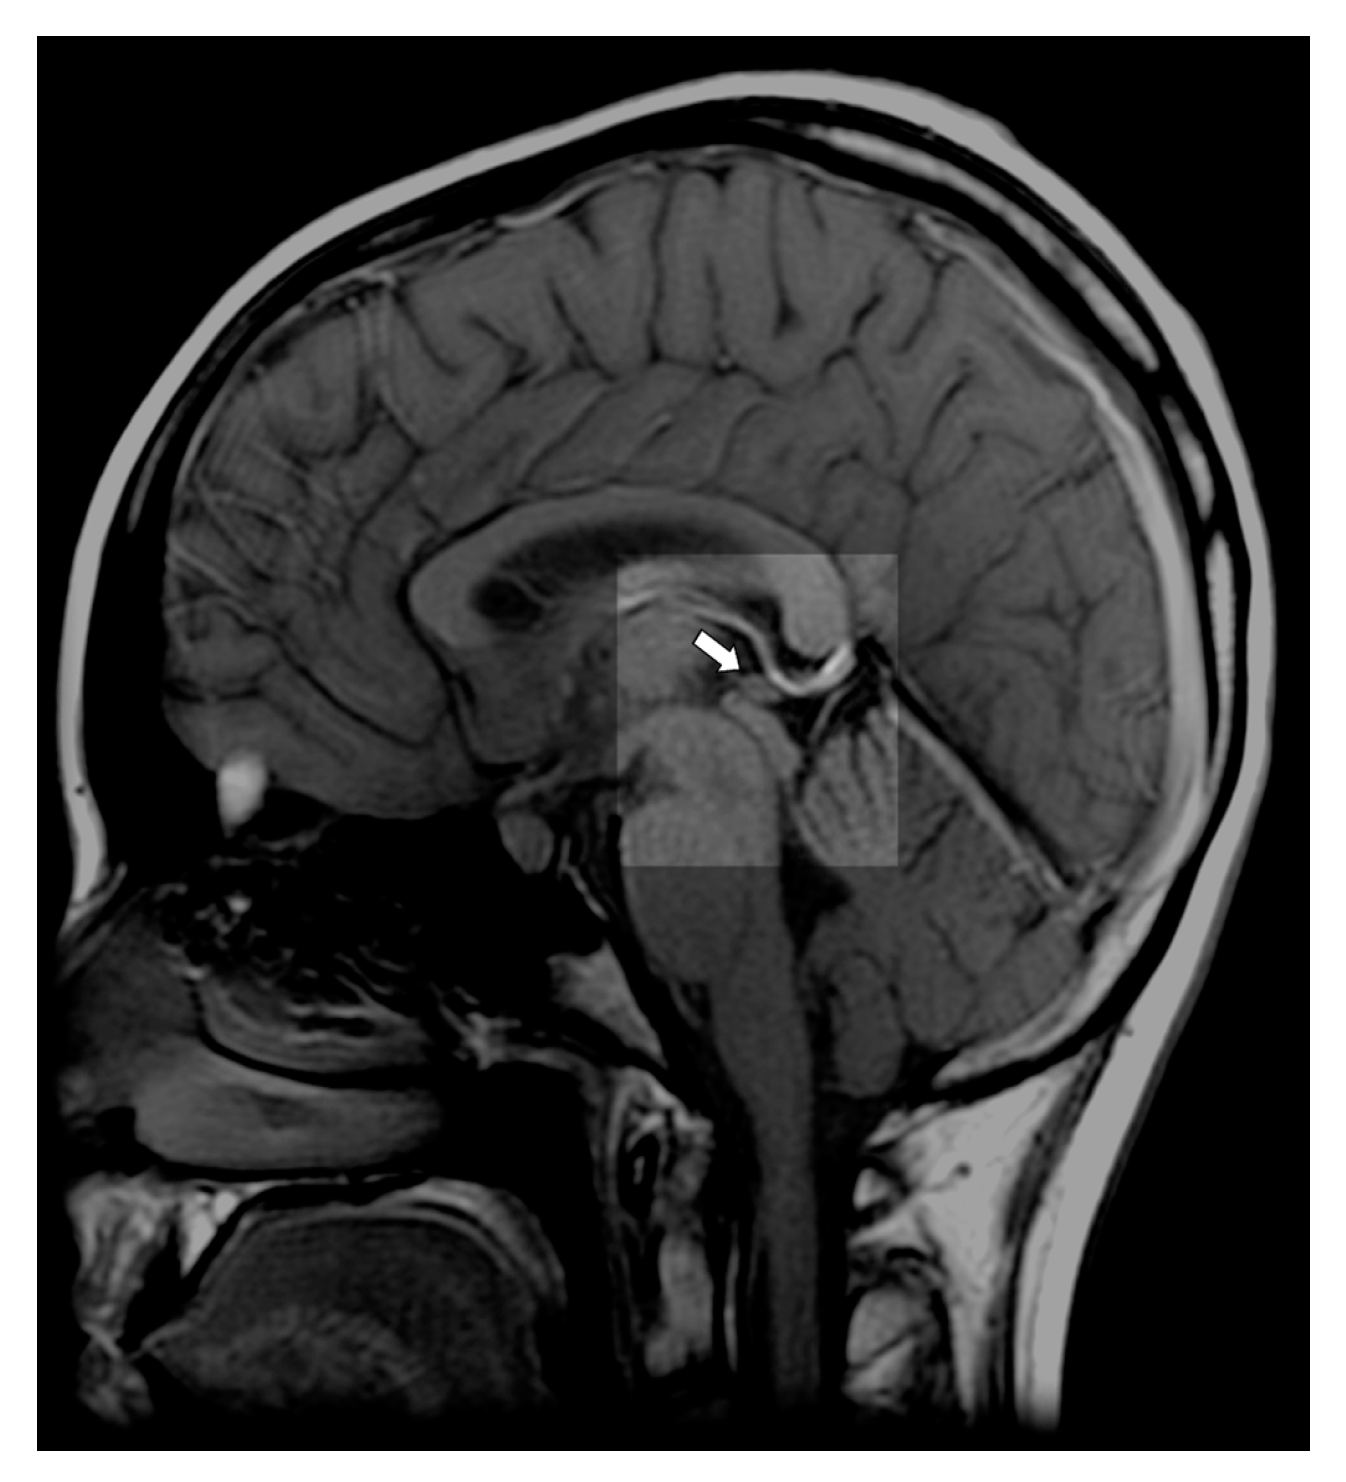

In humans, the pineal gland is a neuroendocrine gland weighing about 150 mg [57]. The organ, part of the epithalamus, is located between the colliculi superiores of the lamina tecti, at the back of the posterior wall of the third brain ventricle [58] (Figure 1). The pineal gland is characterized by a very rich network of blood vessels, which ensures blood flow of 4 mL/min/g, second only to the blood supply to the kidneys [58,59,60]. Another unique anatomical feature of the gland is its location outside the blood–brain barrier [58,59]. Therefore, unlike most other brain structures, the pineal gland has open access to blood and all of its components. Extremely rich vascularization and no significant restrictions in transport from the bloodstream make it possible for the pineal gland to accumulate significant amounts of various substances, mainly, calcium [58,61,62,63,64,65,66]; microelements such as cobalt, zinc, and selenium [67]; and fluoride [52,53,54].

Figure 1.

T1-weighted midline sagittal magnetic resonance imaging (MRI) with an arrow pointing to a normal pineal gland (case courtesy of Assoc Prof Frank Gaillard, Radiopaedia.org, rID: 10767).